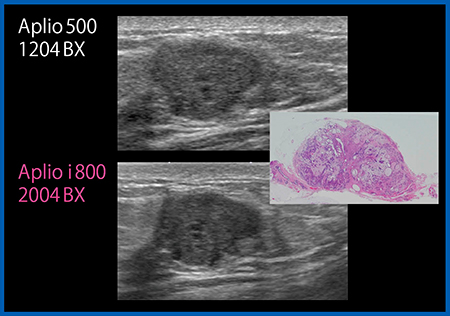

もう一つのリニアプローブ「PLI-2004BX」(8〜24MHz)は,業界最高レベルの高周波を出力でき,かつ従来プローブと同等に深部の観察も可能である。非常に高い分解能が得られ,コメド型DCISでは上皮増生や間質構造,点状高エコーといった内部構造まで観察することができる(図2)。

図2 リニアプローブPLI-2004BX(下)と従来プローブ(上)の画像比較